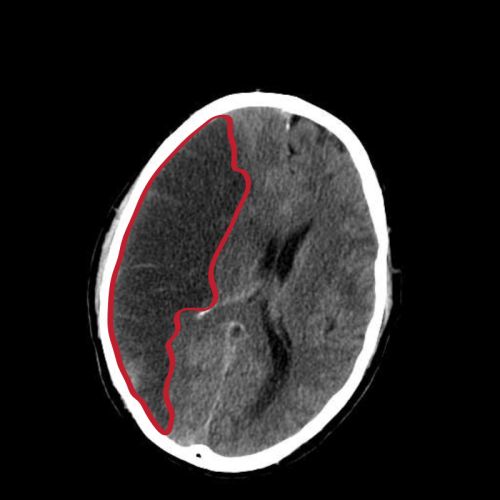

La cardiopatia isquèmica és la malaltia ocasionada per l’arterioesclerosi de les artèries coronàries, és a dir, les encarregades de proporcionar sang al múscul cardíac (miocardi). L’arterioesclerosi coronària és un procés lent de formació de col·lagen i acumulació de lípids (greixos) i cèl·lules inflamatòries (limfòcits). Aquests tres processos provoquen l’aparició d’ateromes o plaques d’ateroma (lesions focals que s’inicien a la capa interna d’una artèria) i amb aquestes, l’estrenyiment (estenosi) de les artèries coronàries (vegeu la figura).

La figura representa un diagrama d’un infart de miocardi, on (2) és la punta de la paret anterior del cor (un infart apical) després de l’oclusió (1) d’una de les branques de l’artèria coronària esquerra (LCA), en contraposició a l’artèria coronària dreta (RCA).

Un accident vascular cerebral (AVC) o accident cerebrovascular, vessament cerebral o ictus cerebral és un episodi agut d’afectació de la circulació cerebral; es produeix una lesió irreversible en un territori cerebral a causa de la pèrdua de flux sanguini al cervell, que produeix una sèrie de símptomes i/o signes variables en funció de l’àrea cerebral afectada. Els accidents cerebrovasculars o ictus (trombosi o vessament cerebral, antigament anomenat apoplexia) són causats per un trastorn de la circulació cerebral, que ocasiona una alteració transitòria o definitiva del funcionament d’una o diverses parts de l’encèfal (vegeu la figura).

L’ictus isquèmic és el més freqüent (entre un 80-85% dels ictus) i es produeix per l’oclusió d’una artèria cerebral; això provoca una disminució del flux sanguini de l’àrea irrigada per l’artèria i, per tant, una lesió parcial o total del parènquima cerebral corresponent.

Per la seva banda, l’ictus hemorràgic, un tipus d’hemorràgia cerebral freqüent, consisteix en el trencament d’una artèria i la subsegüent extravasació de sang a l’encèfal. Representa un 20% aproximadament de tots els ictus. La hipertensió arterial, l’angiopatia amiloide i les lesions vasculars (malformacions arteriovenoses, aneurismes o hematomes intracranials) són els processos causals de base més comuns d’aquesta forma d’ictus. L’ictus hemorràgic lobular es veu sovint en casos d’angiopatia amiloide.